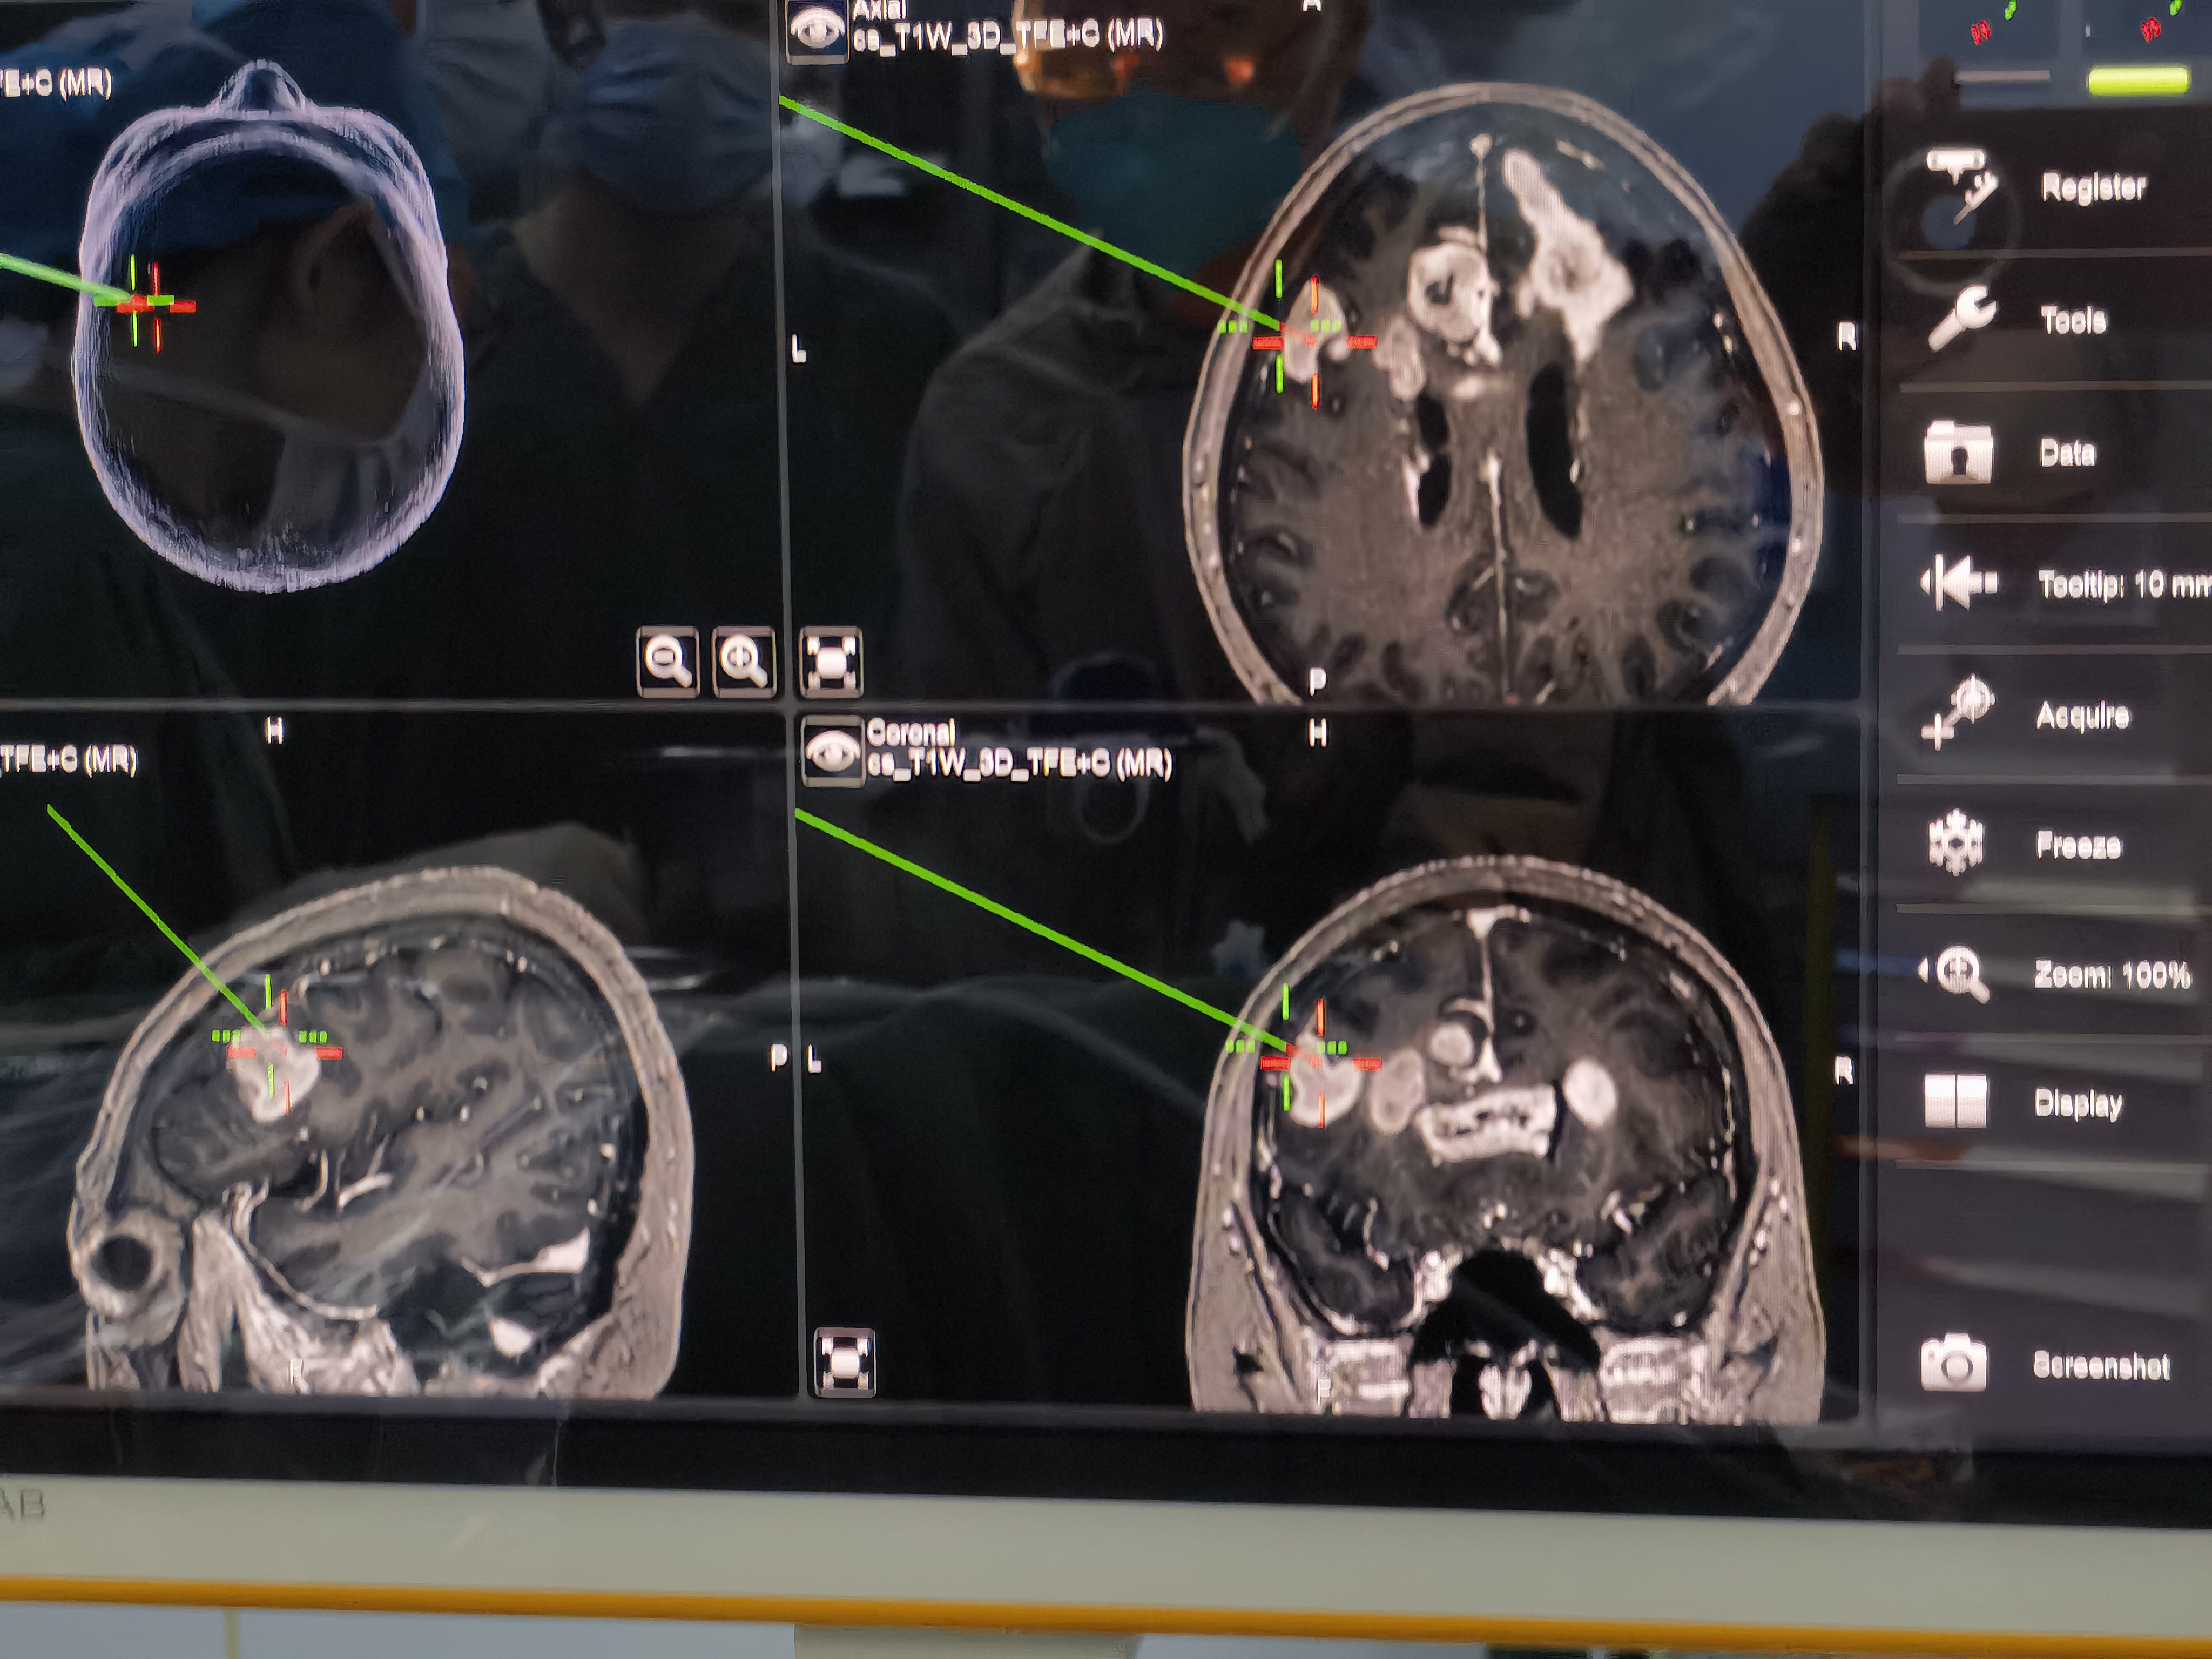

术前增强核磁:

片子可见肿瘤多中心, 累及范围广,包括胼胝体膝部,穹窿体,下丘脑,双侧额叶,左侧脑室前壁。

手术在术中导航下定位。采取双侧骑跨额部骨瓣,先完成左侧肿瘤的切除,然后完成右侧肿瘤切除。